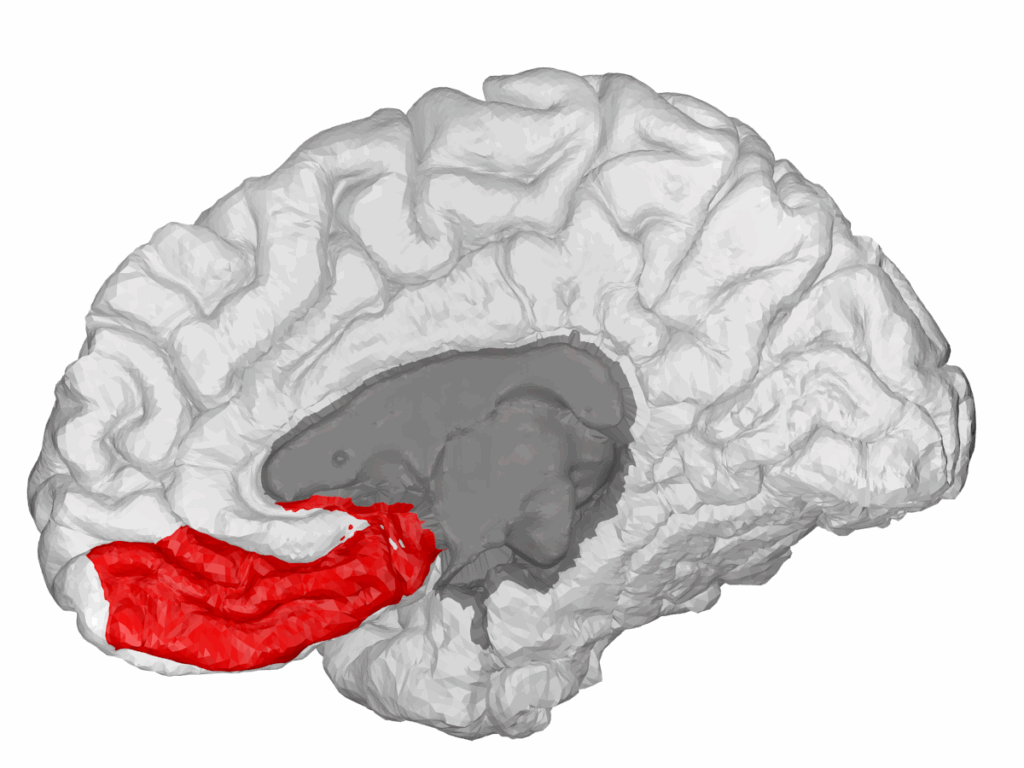

A detailed brain scan highlights the ventromedial prefrontal cortex, the region crucial for value judgment and decision making. | Photo by wikimedia.org

The ventromedial prefrontal cortex (vmPFC) is where logic and emotion intertwine to shape our most personal decisions. This brain region encodes our subjective values—what we find meaningful, rewarding, or important. By integrating emotional input with rational thought, the vmPFC helps us form preferences unique to our experiences and beliefs. Damage to this area can lead to choices that feel disconnected from personal values, highlighting its crucial role in authentic decision-making. Study